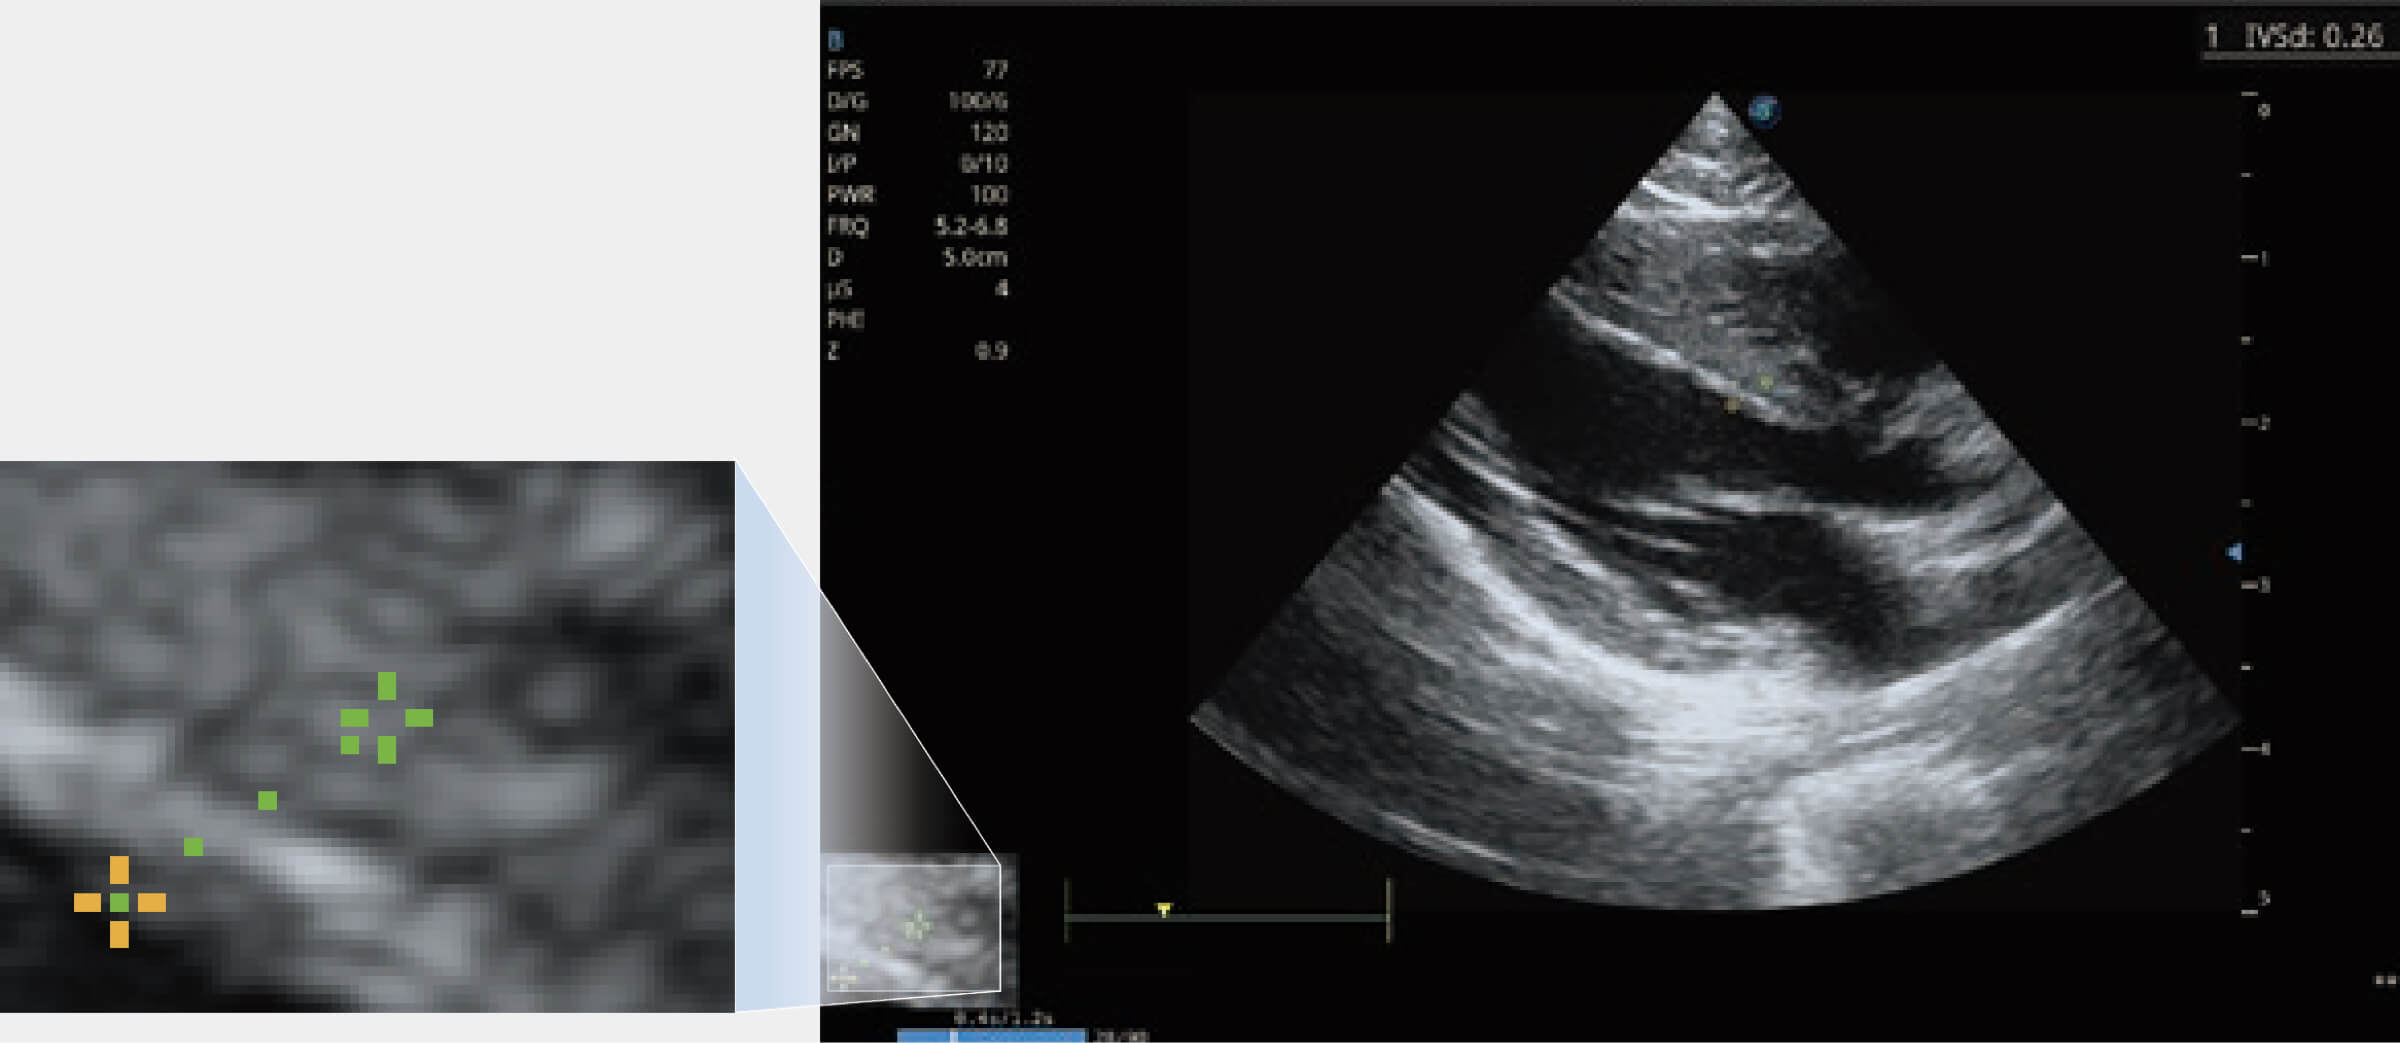

能够基于左心室壁追踪和辛普森法,自动计算射血分数,支持多个可移动点描迹,与手动测量相比,极大节省了动物医生的时间和精力。

当心脏测量结果超出正常范围时,可实时预警提示动物医生,减少疾病漏诊概率。